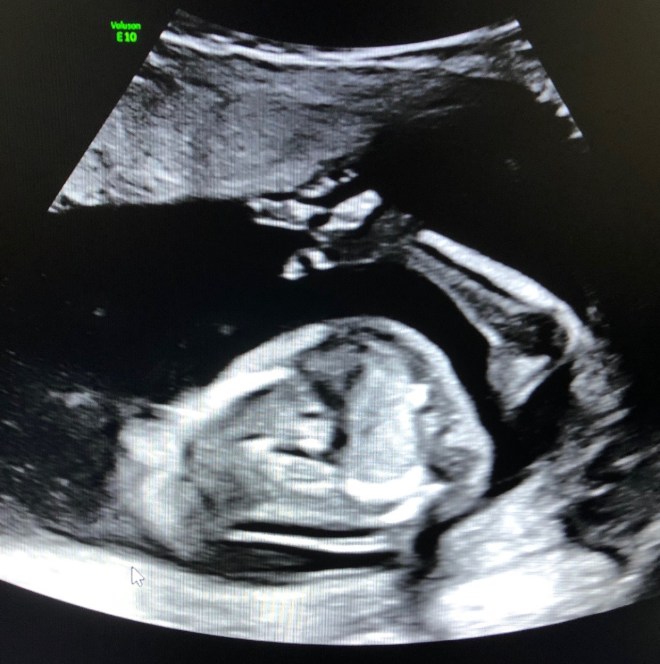

the first half of the appointment consists of the ultrasound where the sonographer takes tons of pictures of baby to measure, track development, look for potential abnormalities or defects, and check if the amniotic wall has fused. then you meet with the doctor to go over the results. little bug (our nickname for this baby) was looking good and happy. per usual, he would not sit still for his pictures! then the doctor came in to talk through the results. things we learned this day: 1) i would not be getting the amnio unless we wanted to risk an unsuccessful procedure (we decided to return in 2 weeks) 2) there were a few areas of concern – there were signs of a hole in his heart, a potential brain defect, and a potential echogenic bowel 3) he was happy as a clam and gave us the thumbs up – like don’t worry mom and dad, i’m going to be okay 🙂 meet little bug ❤